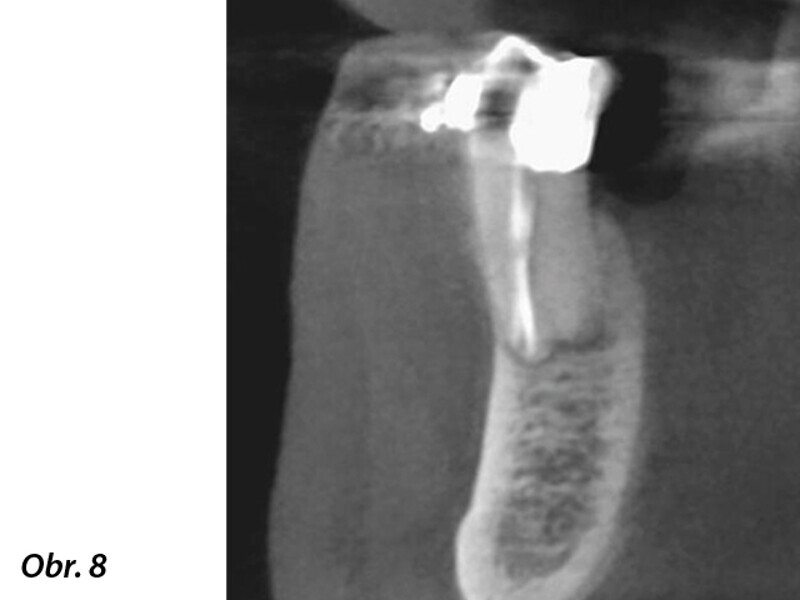

3D technologie v diagnostice a léčbě endodontických onemocnění